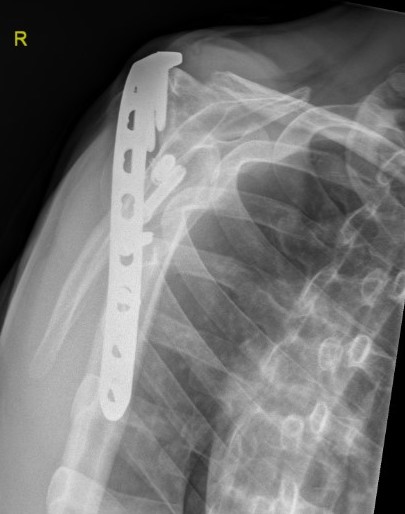

Extra-articular - plate along spine of scapula / acromion and lateral humerus

- supplement with pelvic reconstruction 12 - 14 hole plate scapular spine / acromion / humerus